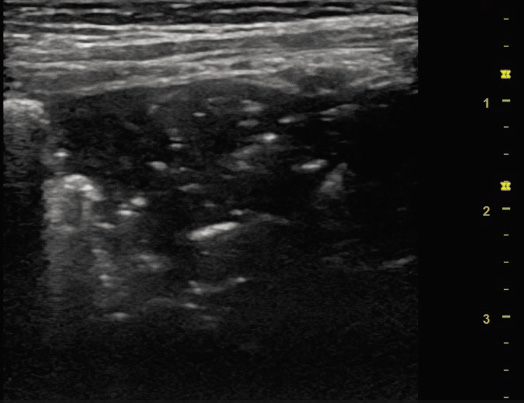

Motivo de consulta: fiebre, tos y mocos. Anamnesis: lactante de 8 meses de vida que acude a la consulta por fiebre máxima de 38ºC, de 48 horas de evolución. Refieren cuadro catarral con mucosidad los cinco días previos, pero en las últimas 24 horas aumento de la tos que le despierta por la noche y le provoca el vómito. Rechazo parcial de la ingesta. Orina y deposiciones sin alteraciones. Antecedentes personales: recién nacida prematura de 34 semanas de edad gestacional. Sin episodios de dificultad respiratoria previos. Exploración física: buen aspecto general, normocoloreada, normohidratada. No exantemas, no petequias. Tiraje subcostal bajo e intercostal leve. ACP: buena entrada de aire bilateral, subcrepitantes en ambas bases pulmonares asociando sibilancias telespiratorias. ABD: blando y depresible, sin masas ni megalias. ORL: otoscopia normal, orofaringe hiperémica con mucosidad en cavum. Pruebas complementarias: combo antígeno VRS, influenza A y B, Mycoplasma y adenovirus (inmunocromatografía): positivo para VRS. Ecografía pulmonar (primera consulta): se observa aumento de líneas B, engrosamiento de la línea pleural, así como consolidaciones subpleurales bilaterales menores de 10 mm (Fig. 12). Figura 12. Plan: tras valoración de la paciente, se recomiendan lavados nasales, postura semiincorporada y administración de salbutamol en cámara, 2-3 pulsaciones cada 8 horas. En caso de persistencia o empeoramiento de la fiebre, control en 48 horas. Evolución: acuden al pediatra a las 48 horas, por persistencia y aumento de la temperatura, con picos de fiebre de hasta 39ºC, aumento de la tos y mucosidad, asociando rechazo de la ingesta mayor que en días previos. Ecografía pulmonar de control a las 48 horas: se observa imagen en dientes de sierra y broncograma aéreo (Fig. 13). Figura 13.